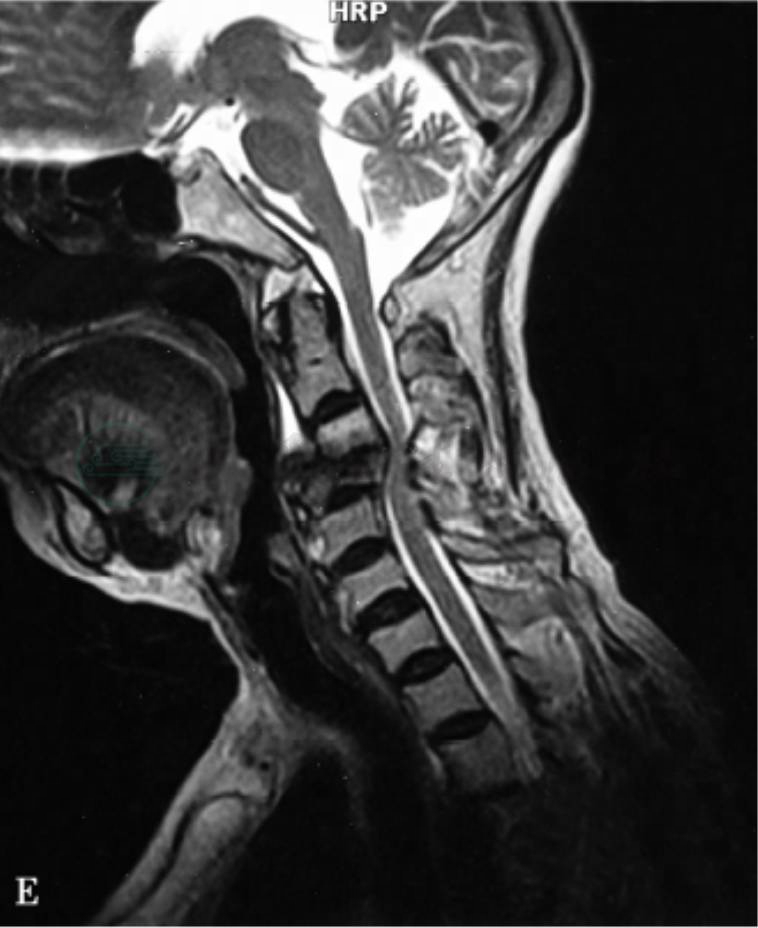

3.MRI

和其他检查技术相比能更早发现颈椎结核病灶。MRI目前多采用自旋回波程序(SE序列),采用矢状位和横断面成像。结核病变侵犯的椎体、椎间盘、椎旁软组织以及椎旁脓肿,在T1WI呈低信号,在T2WI上信号增强,骨皮质模糊。当脊髓受压严重时,可以出现脊髓水肿、软化变性。因此在T2WI上可以见到椎体破坏程度、椎旁脓肿与气管、食管及后方椎管的邻近关系(图3)。Gd‐DT PA增强MRI图像能更清楚地显示椎旁脓肿。

图2 颈椎结核的MRI影像表现

可清楚显示病变与神经之间的关系,椎体骨质破坏,信号不一,形成的脓肿压迫硬膜囊和脊髓

颈椎结核通常发生在前柱,因此前路手术最常用。有文献报道,后路固定可以增加前柱重建的稳定性。但是在发生以下情况时,需要进行前后路联合手术 (图4):①前路病灶广泛并伴有后方硬膜外脓肿;②结核侵犯椎体前后柱;③严重颈椎后凸畸形需要前后路联合手术。

图4 颈椎结核的手术治疗

A、B:术前X线,椎体破坏,有脱位;C、D:CT示椎体破坏;E~G:MRI可显示椎前及椎管内脓肿;H、I:行手术治疗,前方置入髂骨,后方侧块螺钉固定